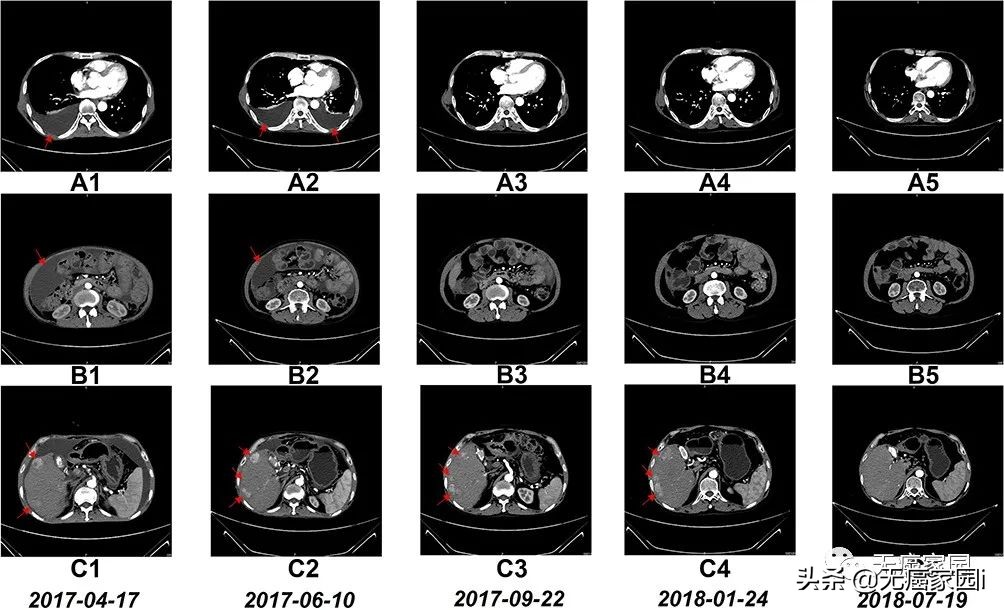

NK细胞治疗前和治疗期间的CT扫描结果

图A1~A5:CT扫描显示,6个疗程后胸腔积液完全消失;

图B1~B5:CT扫描显示,6个疗程后腹水几乎完全消失;

图C1~C5:CT:扫描显示,肝右叶多个肿瘤的大小在17 个疗程后显著缩小;